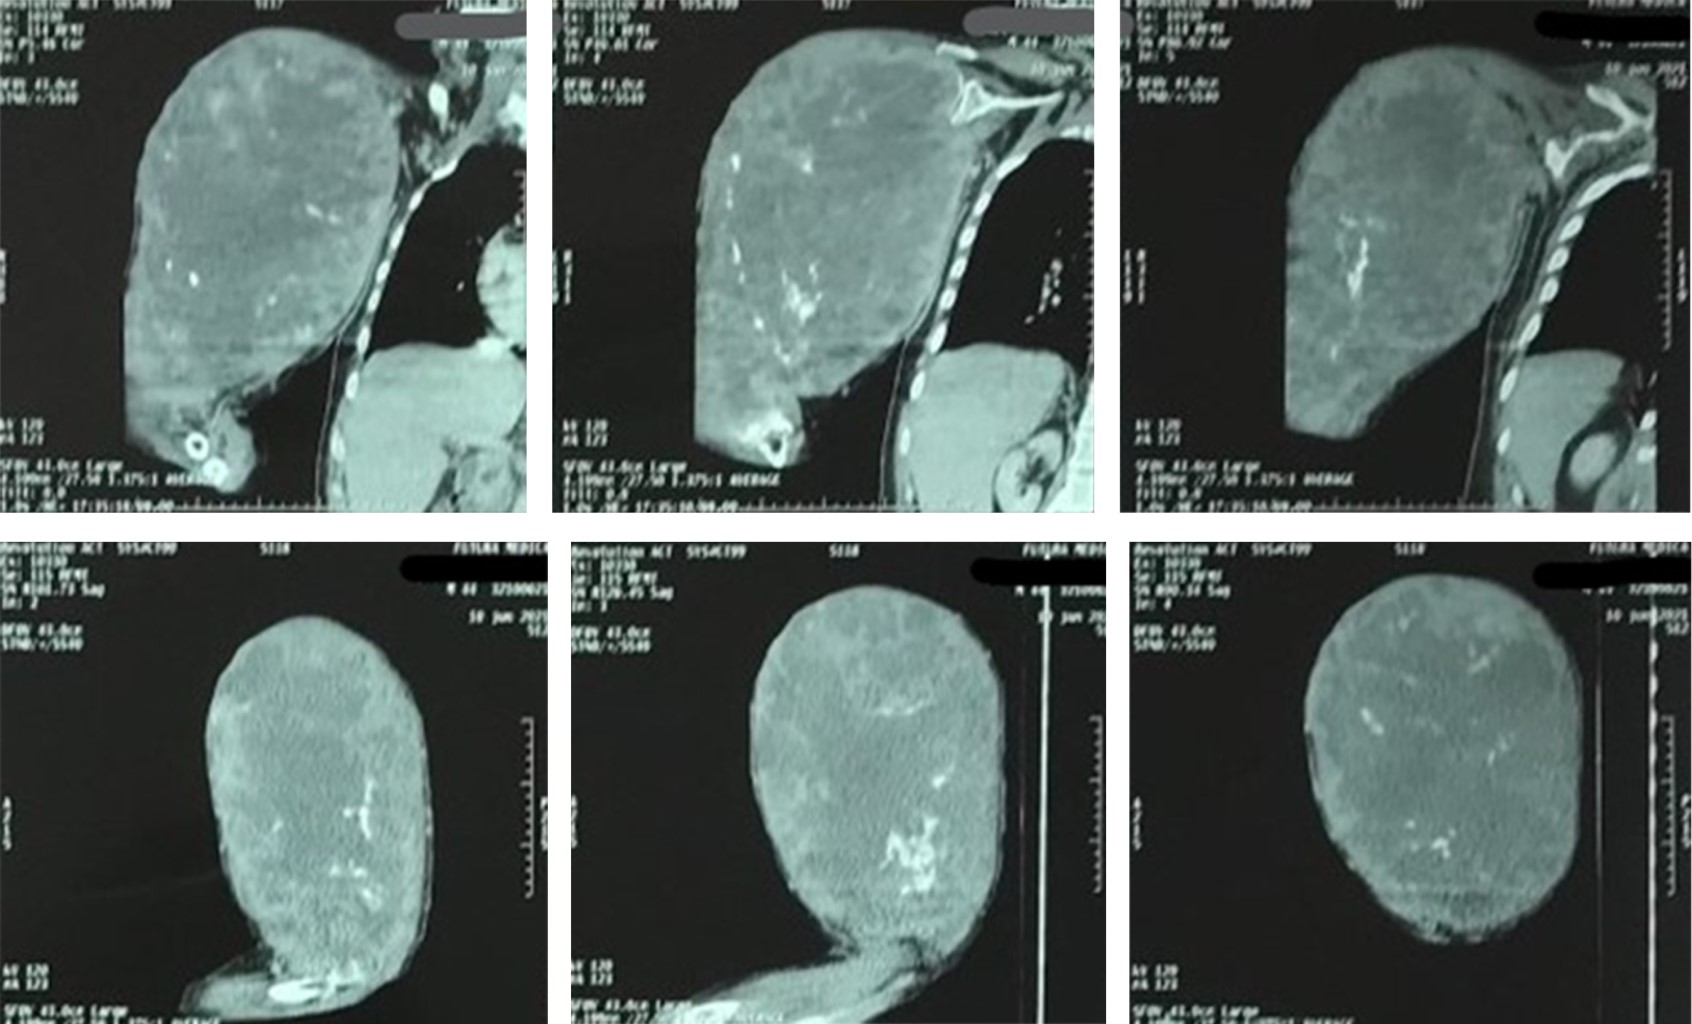

A la exploración física, consciente, orientado, cooperador, con palidez de piel y tegumentos +++. Cuello cilíndrico, móvil, tráquea central, Mallampati modificado II. Bellhouse-Dore: grado 1. Con tumoración de miembro torácico derecho de aproximadamente 30 × 40 cm, a tensión y con trama vascular aumentada, edematizada y dolorosa a la palpación y a la movilización, pulsos radial y cubital ipsilateral disminuido en intensidad. Resto sin alteraciones. Talla: 1.60 m. Peso: 58 kg. Peso predicho: 56.9 kg. Se anexa tomografía axial computarizada (Figuras 1 y 2).

Figura 1